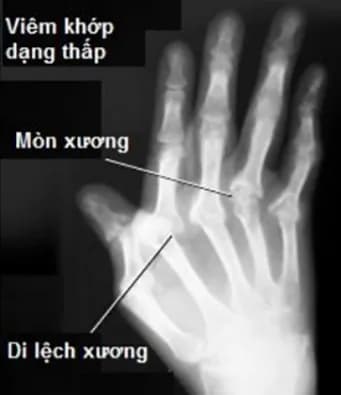

- Viêm khớp dạng thấp nặng ảnh hưởng đến cột sống cổ.